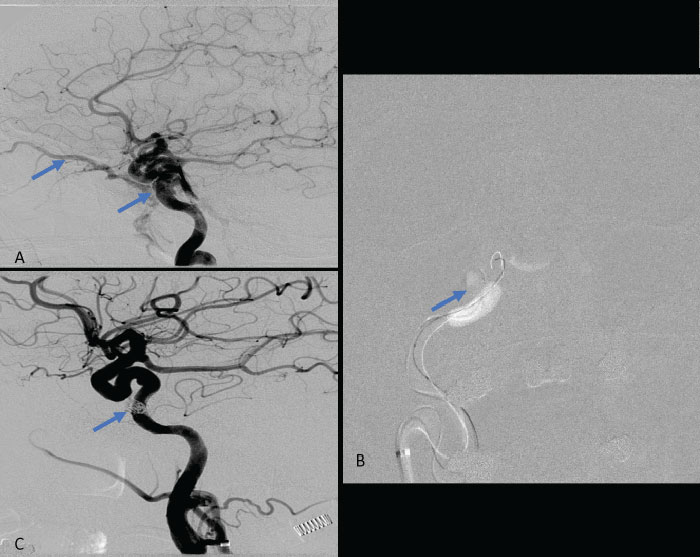

Collateral venous drainage into the orbit and skull base was observed (Fig. A). After successful cannulation of the direct aperture between the right carotid artery and the cavernous sinus, balloon-assisted coil embolization of the posterolateral compartment was performed until the fistula was closed (Fig. B and C). She experienced immediate cessation of her pulsatile tinnitus with the early improvement of the right VI nerve palsy and near-complete recovery of her vision within 6 weeks.

Figure: (A) Right ICA Cavernous Fistula with Venous Shunting (B) Balloon Assisted Coil Embolization (C) Fistula Cured Post Embolization